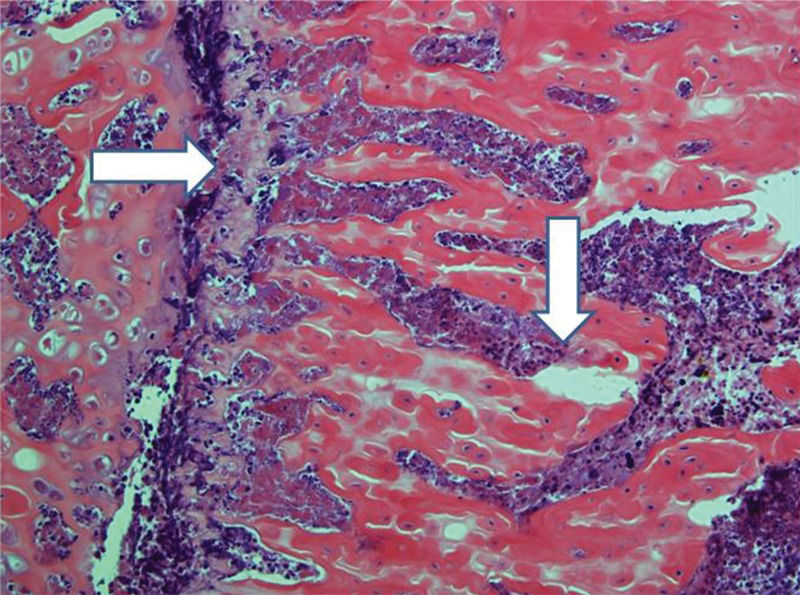

Control femurs exhibited healthy trabeculae and bone marrow histology at all times, as expected (Figure 9). On ischemic slides after 15 days, mild marrow and bone edema could be identified, along with some degree of bone marrow necrosis (Figure 10).

After 30 days, edema was no longer conspicuous. Some areas exhibited bone resorption. The bone marrow did not change substantially compared with that at 15 days (Figure 11). By 60 days, areas exhibiting extensive destruction of the bone and bone marrow could be identified. Nevertheless, as at other time points, the femur showed a generally heterogeneous pattern. Depending on the anatomical location, areas that were in fairly good histological shape were identified, whereas other areas revealed severe damage (Figure 12).

Implanted femur histology, 60 days (H&E, 100 X): Bone (upper arrow) and bone marrow (lower double arrows) degradation is more advanced. However, in keeping with the findings at 15 and 30 days, the pattern is not homogeneous, with seriously damaged areas, along with a better preserved femur.

New bone generation was occasionally detected on histological slides in this experience; however, bone and bone marrow damage constituted the most noticeable features. Nevertheless, one should emphasize the heterogeneity of the results, which was not perceived in the figures in the article because representative images were selected. At all of the follow-ups, but especially after 30 and 60 days, quite healthy areas were prominent, in contrast with heavily compromised skeleton tissue. This finding could be another limitation of the histological monitoring of bone necrosis because the interpretation of biopsy material would become dependent on regional fluctuations in tissue damage.